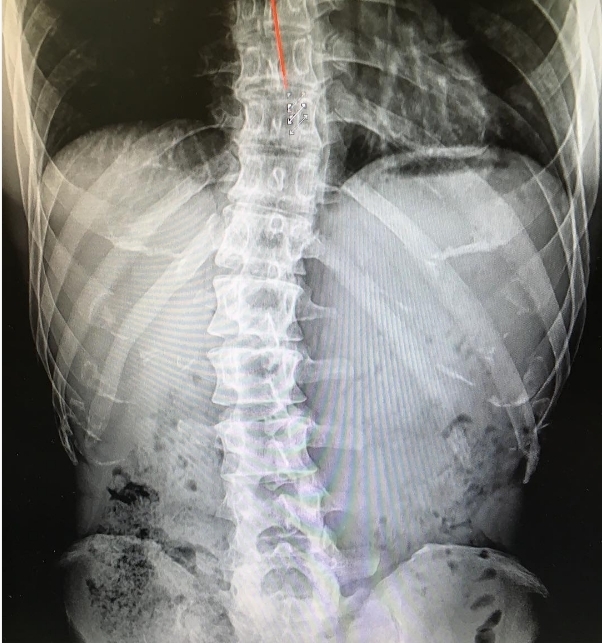

在韩国综艺节目《Running Man》大受欢迎的金钟国,早前曾在Instagram分享自身的X光片,透露自己一直受椎间盘突出影响,为了减轻痛楚,只好一直健身。